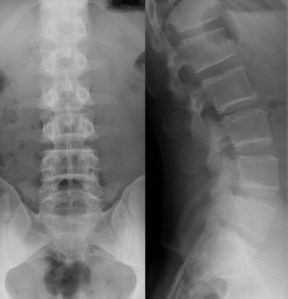

X-ray